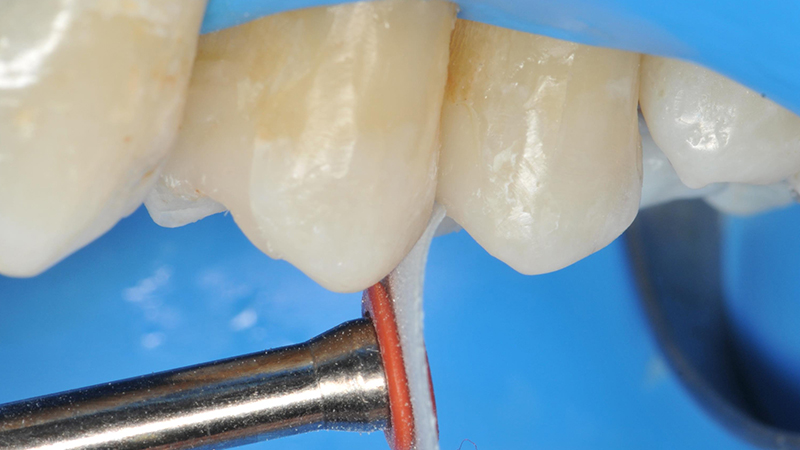

posizionamento di due matrici sezionali per ottenere dei punti di contatto corretti e adeguati

Fig. 3 - Dopo la preparazione della cavità, sono state posizionate due matrici sezionali su ogni cavità per ottenere dei punti di contatto il più possibile corretti e adeguati. Successivamente le matrici sono state bloccate con un cuneo di legno arancione.

La parte esterna del cuneo è stata spezzata per fare in modo che rimanesse solo nella zona interprossimale

Fig. 4 - Successivamente, la parte esterna del cuneo è stata spezzata per fare in modo che quest'ultimo rimanesse solo nella zona interpersonale.

l'anello utilizzato spingeva la matrice nel modo più forte possibile contro la superficie del dente, ripristinando le corrette proporzioni dei due denti

Fig. 5 - In questo modo, l'anello utilizzato spingeva la matrice nel modo più forte possibile contro la superficie del dente, ripristinando le corrette proporzioni dei due denti. Questo aspetto è molto importante per fare in modo che la matrice sigilli in modo adeguato la cavità di II classe.